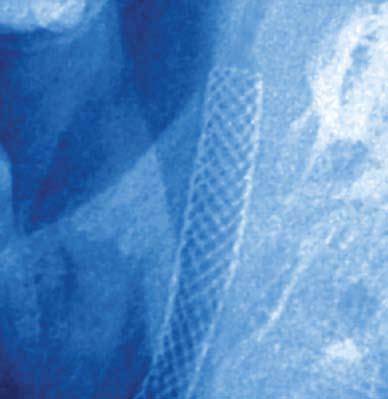

Vascular dementia, as it is known in stroke patients, mirrors the symptoms of Alzheimer’s disease—the mood swings, the loss of recognition of familiar places and faces, the sometimes inappropri- small, doctors usually place a fine mesh tube, called a stent, into the artery to support the arterial walls and reduce the chance that the artery will close. A filter is put in place to remove large pieces of plaque from the blood that could reach the brain and cause a stroke.

The procedure, however, still allows tiny pieces of plaque, 100 microns or less, to reach the brain. Although that amount of plaque fails to cause stroke or dementia outright, researchers now believe the presence of plaque in the brain can predispose a person to vascular dementia in five to 10 years. A new procedure performed by Emory doctors can unclog the carotid artery and, at the same time, prevent any plaque from reaching the brain.

Commonly, stroke patients are treated with angioplasty. During the procedure, a balloon is inserted into the carotid artery to compress the plaque and widen the passageway. Unless the artery is too

In a clinical trial to test the Parodi antiembolism system (PAES), a device is inserted in the artery, and a balloon is inflated just below the clogged portion. “This prevents forward blood flow to the brain during the angioplasty and stenting, thereby preventing any plaque from reaching the brain,” says Karthikeshwar Kasirajan, left), an Emory vascular surgeon who uses the PAES, which is also known as NPS, or neuro protection system. With this approach, a second catheter is inserted in a vein near the femoral artery that allows for reversal of the blood flow. As the blood travels in the opposite direction, surgeons essentially siphon the blood, filtering out all the plaque before returning it to the body through the femoral vein. Because there is no plaque reaching the brain, a patient’s chance of having a stroke is greatly reduced.

Clinical trials led by vascular surgeon Juan Parodi, who invented PAES, showed less than 2% stroke occurrence with the carotid stent with retrograde blood flow. By comparison, patients who underwent carotid stenting with a distal filter had a stroke rate of 9.6%.

In a second NPS clinical trial in which Emory participated, 40 patients received the flow reversal system. All are doing well, says Kasirajan, who trained with Parodi at Cleveland Clinic. —Kay